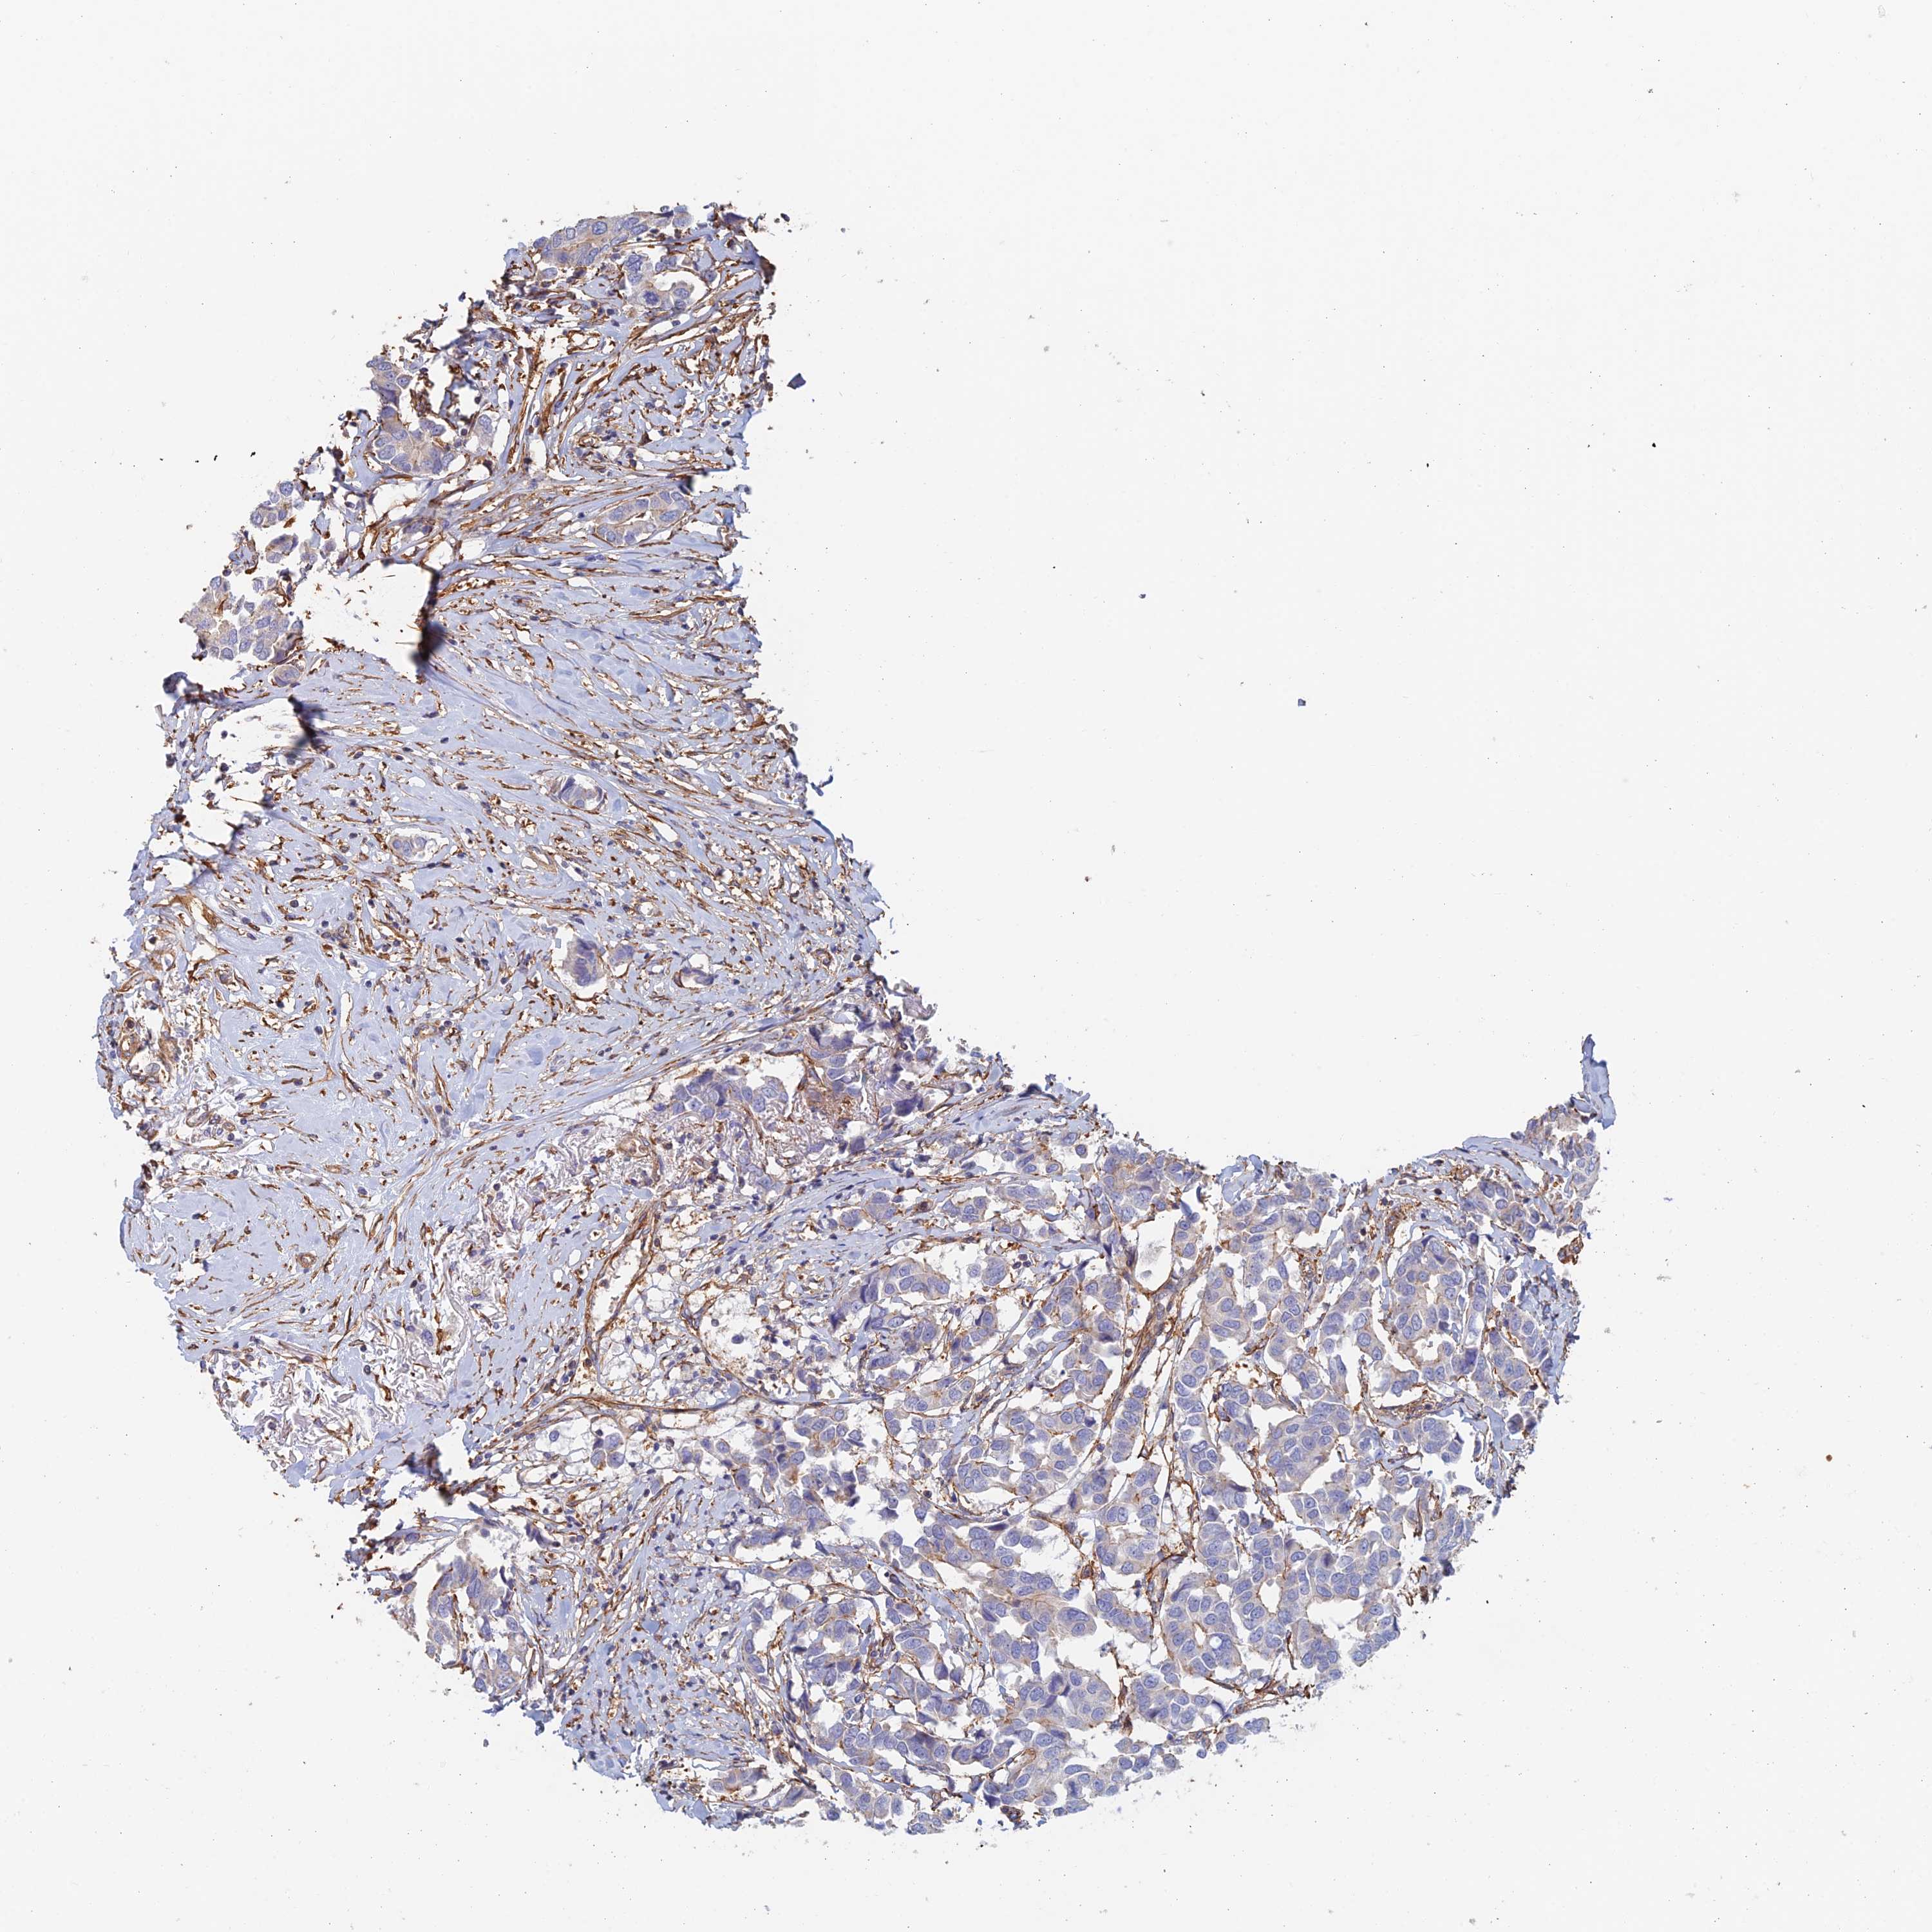

CANCER BREAST CANCER Show tissue menu

BRCA TCGA BRCA VALIDATION PROTEIN EXPRESSION

Breast cancer

Human cancer